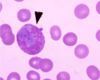

Neutrophil